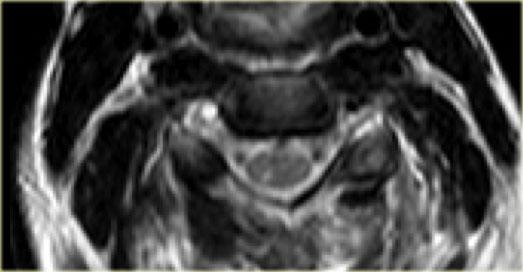

Tiếp tục với hình ảnh mặt cắt axial.

Hình ảnh axial cho thấy tổn thương tủy sống và ngoài ra còn có sự vắng mặt của khoảng trống dòng chảy (flow void) ở động mạch đốt sống phải.

Điều này gợi ý huyết khối do bóc tách động mạch.

Kết luận, bệnh nhân này không có gãy xương, nhưng có bong gân tăng gấp nặng kèm thoát vị đĩa đệm cấp tính, tổn thương tủy sống không xuất huyết và huyết khối động mạch đốt sống.

Chụp mạch cộng hưởng từ (MRA) xác nhận tắc nghẽn động mạch đốt sống phải.